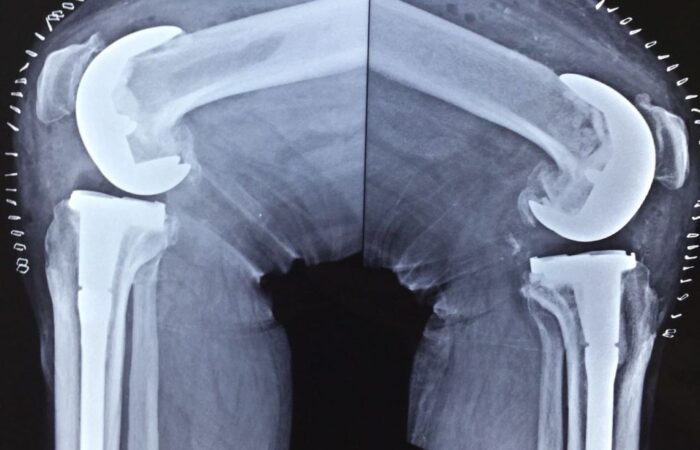

X-rays of patient of bilateral knee replacement in one sitting before and after surgery

Post Operation X-rays